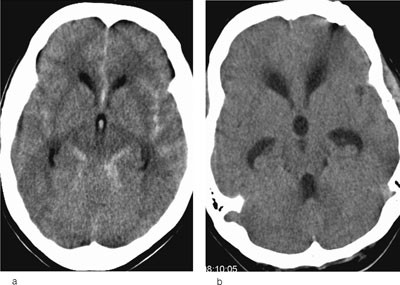

Cerebral CT er den raskeste og mest sensitive metoden for påvisning av subaraknoidalt blod (fig 1a). CT-angiografi med moderne spiral-CT og intravenøs kontrast er den for tiden beste undersøkelse for aneurismepåvisning (6). Cerebral angiografi blir fortsatt gjort der CT-angiografi ikke kan påvise aneurisme. Ved sikker subaraknoidalblødning uten påvist årsak gjøres det ny CT-angiografi etter en uke og, hvis denne er negativ, etter ytterligere 2 – 3 uker.

Hydrocephalus betegner tilstander hvor det er et misforhold mellom produksjon og eliminasjon av cerebrospinalvæske. Subaraknoidalt og/eller intraventrikulært blod blokkerer spinalvæskens passasje mot de steder den kan bli resorbert. Hjerneventriklene vil bli utvidet. Slik akutt hydrocephalus kort tid etter subaraknoidalblødning ses hos 50 % (fig 1b), den kan være livstruende og behandles på kort sikt med ekstern ventrikkeldrenasje. Pasienter som blir verre når drenet stenges kan trenge shuntoperasjon, som er en varig spinalvæskedrenering til for eksempel peritonealhulen.